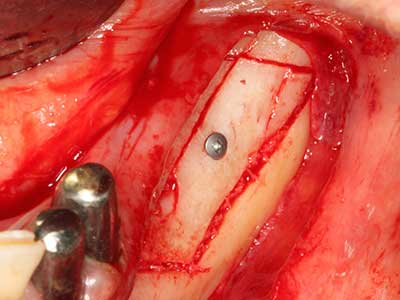

El tejido óseo no solo tiene un contenido puramente mineral, sino que también presenta una importante proporción de fibras de colágeno. Esto no solo garantiza una buena resistencia a la presión, sino también una cierta flexibilidad, que puede aprovecharse para la realización de aumentos. En la plastia de expansión clásica a efectos de una partición ósea, la cresta maxilar atrofiada se divide en su eje longitudinal y, tras alcanzar una profundidad de osteotomía suficiente, se extiende con cuidado (fig. 13-16), en un caso ideal sin desperiostizar de forma visible el maxilar (Brugnami, Caiazzo et al. 2014, Stricker, Fleiner et al. 2014). Los sistemas de tornillos y placas con distancia de expansión creciente han demostrado su eficacia para distanciar entre sí las dos tablas óseas por debajo del umbral de rotura. Por regla general, se requieren anchuras de hueso residual de al menos 3 a 4 mm (Chiapasco, Zaniboni et al. 2006) para garantizar una flexibilidad y una cobertura ósea suficientes de los implantes que van a incorporarse. En caso necesario, una osteotomía de descarga vertical unilateral o bilateral puede mejorar la flexibilidad. Como alternativa a la técnica clásica se ha descrito una combinación con otras técnicas de aumento, sobre todo en la parte bucal.

Con el uso de sierras piezoeléctricas la división se efectúa de forma especialmente cuidadosa y sin pérdidas importantes de las dimensiones, por lo que no se han encontrado diferencias significativas entre los implantes realizados en el maxilar dividido y en la cresta alveolar no deficitaria (Chiapasco, Zaniboni et al. 2006, Danza, Guidi et al. 2009). No obstante, precisamente en la partición profunda y limitada de forma local, es preciso asegurarse de que exista una adecuada irrigación por agua para evitar que se produzcan sobrecargas térmicas en las áreas de osteotomía apical.